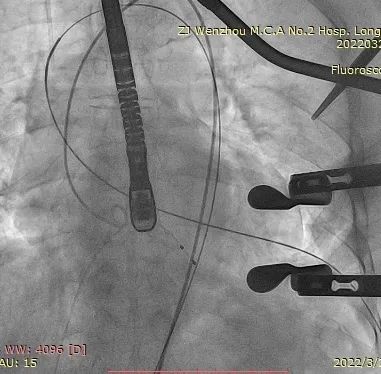

经股静脉置入临时起搏器,并经股动脉植入6F猪尾管。行第五肋间小切口并在心尖部缝制荷包。穿刺心尖后进泥鳅导丝过主动脉瓣经过主动脉弓到达降主动脉膈肌水平。单弯管交换硬导丝后,用16F扩张鞘预扩心尖穿刺处,后将 J-Valve瓣膜(27mm)装入输送器并经心尖穿刺处推送至主动脉根部,释放定位件,并微调角度使其入窦,后完全释放瓣膜,撤出输送器。通过DSA和TEE观察人工瓣膜膨胀后金属支架的形态、位置,有无瓣周漏。撤出导丝,收紧心尖处荷包线并打结,后鱼精蛋白中和肝素,彻底止血,逐层关胸,封皮,拔出股动脉鞘并在股动脉穿刺处压迫止血。手术过程顺利,患者生命体征平稳。

术中影像监护与评估(DSA&TEE)

加硬导丝建立轨道

介入器过瓣环平面